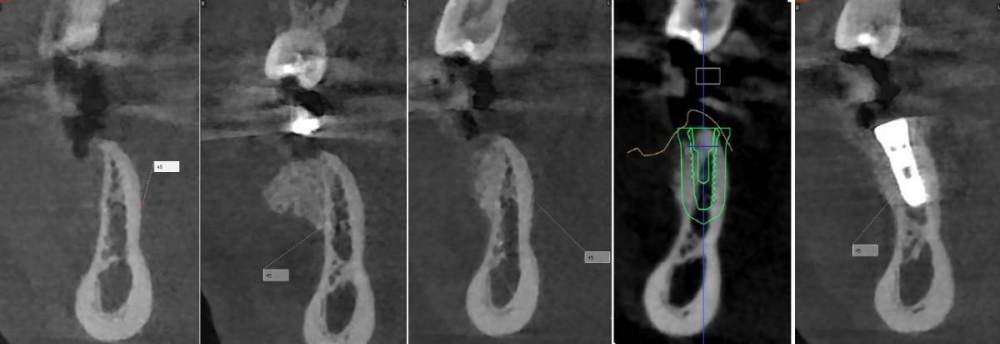

kramer Опубликовано 26 июня, 2023 Поделиться Опубликовано 26 июня, 2023 Первые три снимка в каждом ряду это до, сразу после, через 3 месяца? Ссылка на комментарий

karasov Опубликовано 26 июня, 2023 Автор Поделиться Опубликовано 26 июня, 2023 8 минут назад, Женька сказал: что за магия вне Хогвартса и как это держится?) у ТЛ осстем набор и имплантоводы подходят под хирургический шаблон?? Или мукотом и вслепую без шаблона? Вертикальный разрез кпереди от дефекта, отслаивание слизисто-надкостничного лоскута тупо кзади от разреза, введение в него шприцом графта, два шва. Графт введен вслепую с избытком-позже он лизировался,что видно на кт. SS устанавливаю стандартным набором oneguide, докручиваю имплантоводом от SS. 1 час назад, kramer сказал: Первые три снимка в каждом ряду это до, сразу после, через 3 месяца? До,сразу после, через 3 месяца, планирование, контроль Ссылка на комментарий